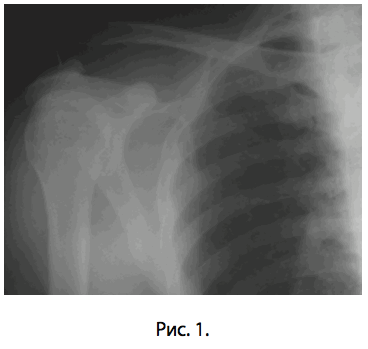

В травматологическое отделение ГКБ им. С.П.Боткина поступил пациент А.А.Ф., 37 лет (и.б. No1068) с травматическим полным вывихом акромиального конца правой ключицы шестидневной давности (рис. 1). Предоперационное обследование заняло двое суток.

Рис. 1- Разрыв акромиально-ключичного сочленения.

Наиболее распространенная причина вывиха акромиально-ключичного сочленения - это прямое падение на плечо . При таком падении повреждаются связки, окружающие и стабилизирующие акромиально-ключичное сочленение.

Если удар достаточно сильный, происходит разрыв связок, отходящих от нижней стороны ключицы. Это вызывает "разъединение" ключицы и лопатки (рис.1). Лопатка смещается вниз под весом руки, в результате чего появляется "шишка", или бугорок, над плечом.